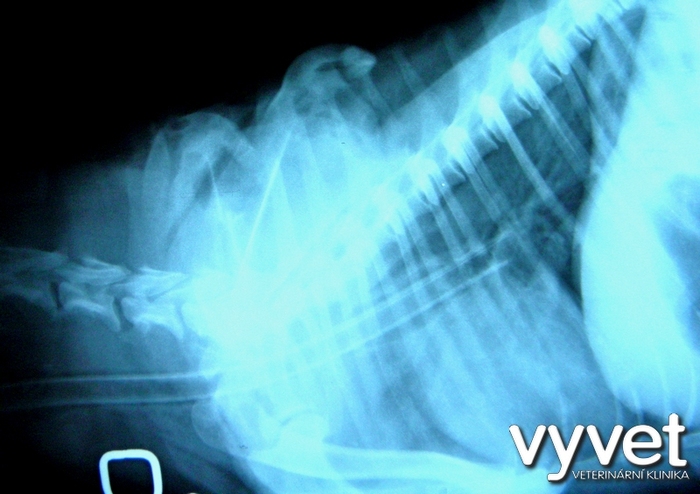

RTG – dobře viditelný fragment (úlomek) lopatky, vzniklý kousnutím.